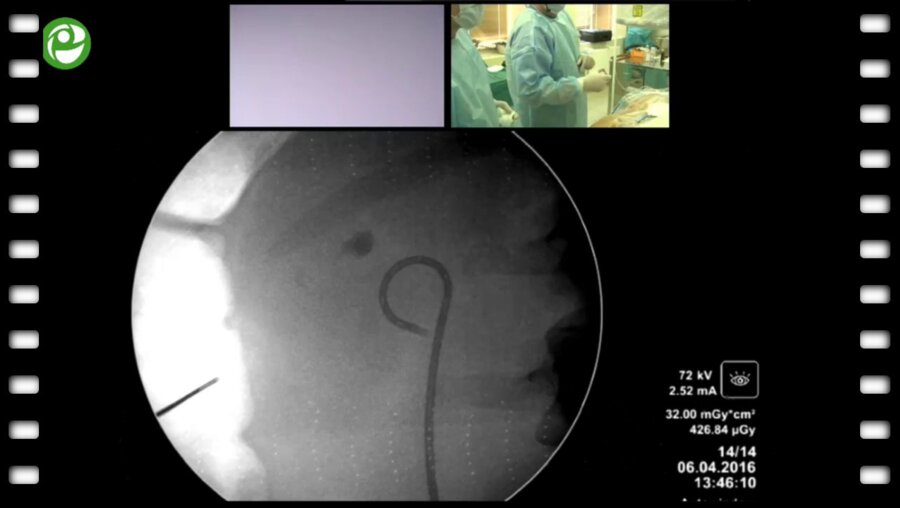

Мастер-класс по перкутанному лечению камней почки

06 апр 2016

3096 просмотров